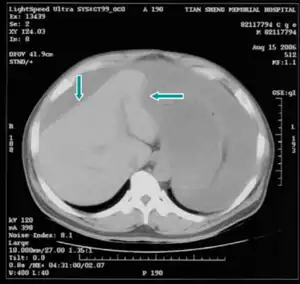

| Computed tomographic scan of an abdomen showing pseudomyxoma peritonei with multiple peritoneal masses (arrow) with "scalloping effect" seen. | |